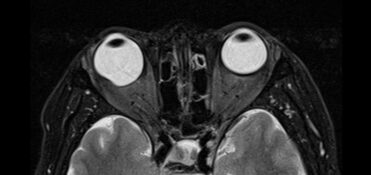

Cortes axiales de resonancia magnética de órbitas en el cual se aprecia aumento del tamaño del globo ocular derecho a expensas de su eje anteroposterior, acompañado de adelgazamiento de su pared posterior lo cual corresponde a estafiloma.

Hallazgos por imagen: Aumento del tamaño del globo ocular y adelgazamiento de sus paredes posteriores.